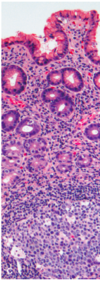

Presence of _________ above the basement membrane in direct contact w/ epithelial cells is abnormal in all parts of the GI tract and signifies active inflammation (gastritis)

Neutrophils

What is the charactestic profile of foveolar cells and the epithelium in acute gastritis?

- Foveolar cell hyperplasia w/ corkscrew profiles

- Epithelial proliferation

Most common cause of chronic gastritis?

Morphology of this organism?

- H. pylori

- Spiral-shaped, curved bacilli

How does atrophic gastritis caused by H. pylori differ from chronic gastritis?

Has a mutlifocal pattern of injury